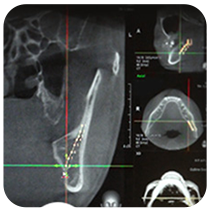

네비게이션 시스템

신경선 검진